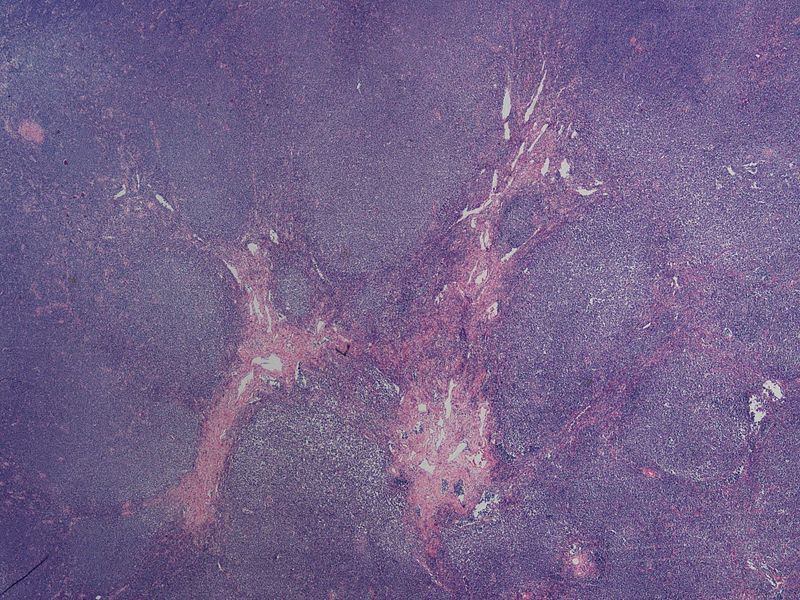

Lymphomas are the most typical reason for a testicular mass in a male over 60-years-old.

Testicular involvement by lymphoma is usually bilateral.

Diffuse large B-cell (DLBCL) type is the most common type of lymphoma to involve the testes.